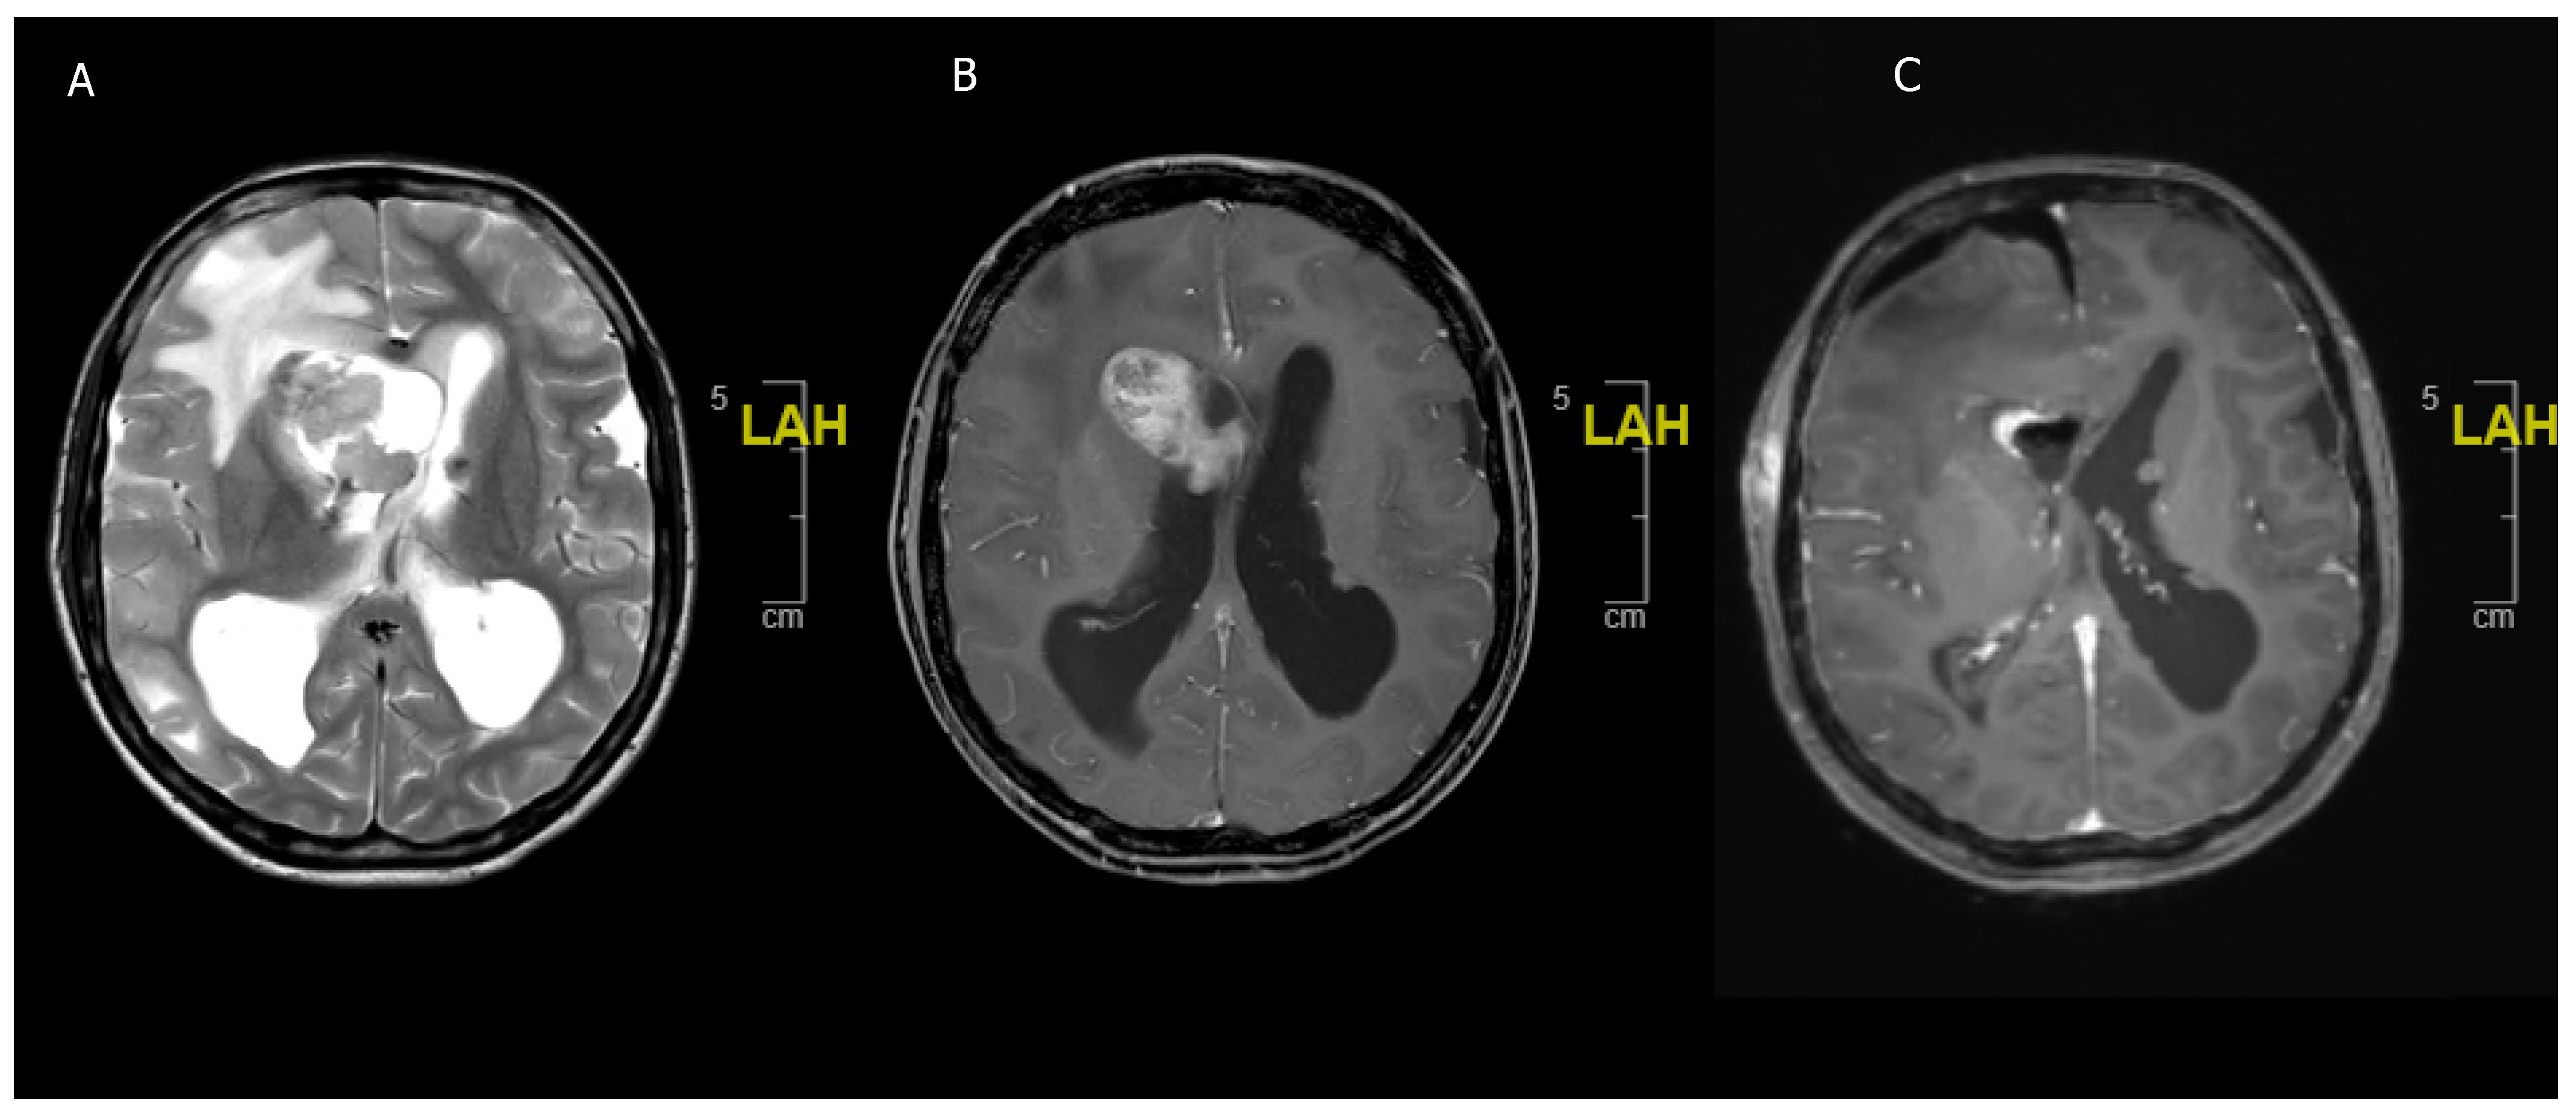

Figure 4. An 8 year-old girl undergoing treatment for congenital scoliosis. (A) MRI head carried out in the setting of her scoliosis work-up showed an incidental finding of a T2 hyperintense cerebellar lesion (B) Interval scan after 6 months showed a spontaneous regression of the lesion. No resection or biopsy was attempted.

5.2. Spontaneous Regression in pLGG

The phenomenon of spontaneous regression has been described in some reports on pLGG but it is basically non-existent in adults. In a case series by Ogiwara, a total of 30% of all partially resected cerebellar pLGG demonstrated spontaneous regression over a median time of 11.9 months [99]. Similar rates (32.5–48%) of spontaneous regression or arrested growth have been described in other case series of cerebellar pLGG [100,101] (Figure 4). This could warrant the decision not to chase the tumor into eloquent regions, such as the peduncle or parts of the brainstem, to avoid postoperative morbidity [99]. Telomerase shortening and the induction of apoptosis are hypothesized to cause growth arrest and the telomere length could offer some prognostic value in pLGG; however, further studies are needed to elucidate this matter [102].

Spontaneous regression is observed in around one third of pLGGs but not in aLGG. This warrants the concept of avoiding radical tumor resection in eloquent regions in children with suspected or confirmed LGG.